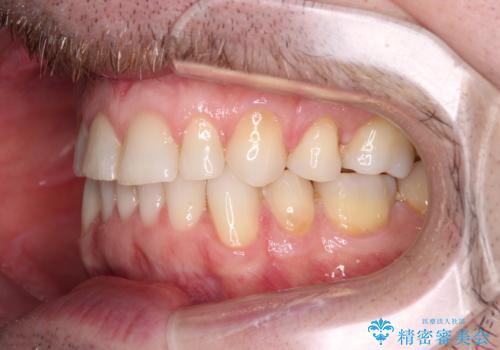

- 上下前歯の叢生を気にして来院された患者様です。

抜歯矯正をした後戻りということで、歯列不正はそれほど大きくなかったため、インビザライン・ライトを用いて矯正治療を行うこととしました。

前歯のデコボコが残っており、シミュレーション通りに動いていない部分がありましたが、再矯正であることやご本人の満足いくところまでデコボコが改善されたとのことで、治療を終了することとしました。